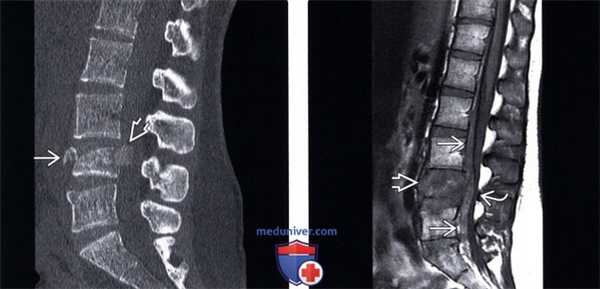

(Слева) КТ, сагиттальный срез: оскольчатый взрывной перелом тела L4 позвонка со смещением фрагмента кпереди и выраженным смещением одного из фрагментов кзади.

(Справа) На Т1 -ВИ отмечается снижение интенсивности сигнала тела L4 позвонка на фоне его перелома. Смещенные кзади фрагменты сдавливают вентральную поверхность дурального мешка, имеет место значительных размеров эпидуральная гематома. Таким образом, выраженная компрессия дурального мешка связана со смещением фрагментов в спинномозговой канал и эпидуральной гематомой.